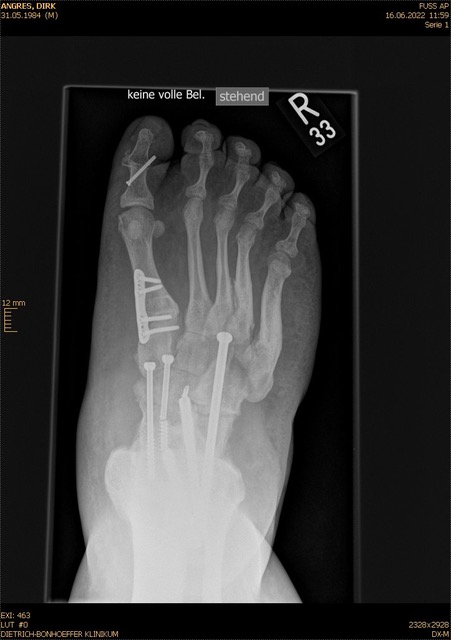

• Fuß belastet dp und seitlich (Abb. 14 und 15)

Typische Merkmale der Standard-dp-Röntgenaufnahme des Fußes im Stand

• Talus und Calcaneus verlaufen fast parallel

• Os naviculare ist gegenüber dem Talus nach medial gedrängt

• Metatarsalia überlappen sich basisnah

• Metatarsale I erscheint verkürzt

• Metatarsus adductus